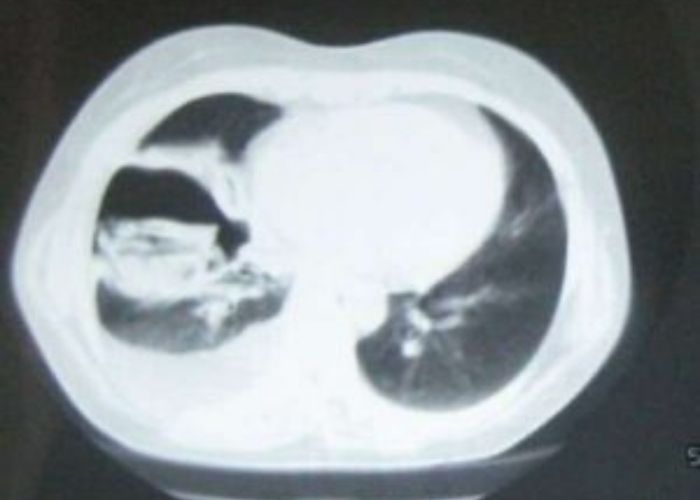

Bronkojenik kistler genellikle mediastende, akciğer parankimi içinde ve nadiren de diafragmaaltı gibi değişik loka-lizasyonlarda bulunan doğumsal iyi huylu kistik oluşumlardır. Her yaş grubunda görülmekle birlikte semptomatik olanlar yenidoğan döneminden itibaren tanınabilirler.

Semptomatik olanlar yenidoğan döneminden itibaren tanınabilirler. Asemptomatik olanlar ise ileri yaşlarda tesadüfen çekilen akciğer grafilerinde ya da başka bir amaç ile çekilen toraks BT tetkikinde tesadüfen saptanırlar.